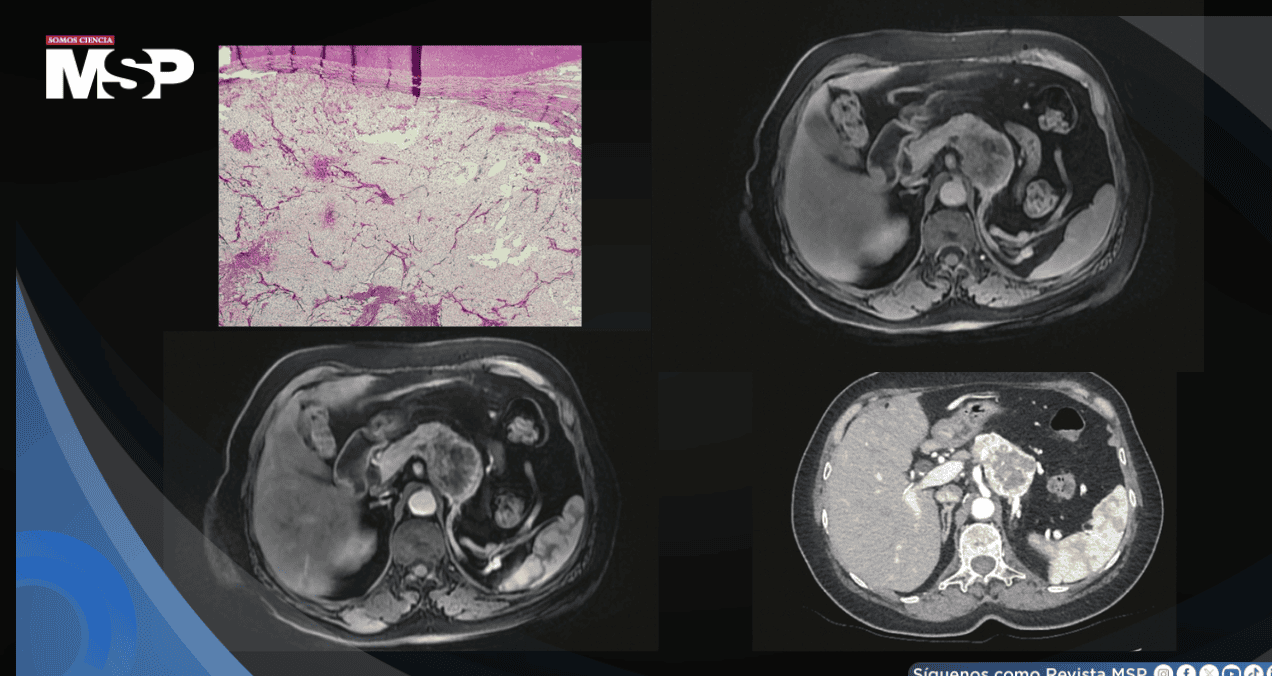

Para caracterizar esta masa, se le realizó una resonancia magnética abdominal, la cual reveló la presencia de un tumor renal de gran tamaño (15 x 10 x 12 cm) en el riñón izquierdo. Este tumor presentaba características de agresividad local, como la rotura de la cápsula del riñón y, de manera más preocupante, había invadido la vena renal izquierda y la vena cava inferior, formando un trombo tumoral que se extendía unos 7 cm.

Una tomografía computarizada de tórax y abdomen confirmó estos hallazgos y mostró, además, cuatro pequeños nódulos pulmonares que en ese momento se consideraron inespecíficos. Con estos datos, el tumor se clasificó como T3cN0M0.

El análisis histológico definitivo del tumor extirpado confirmó que se trataba de un carcinoma de células renales de células claras, con una estadificación patológica de pT3cN0M0. Tras la cirugía, la paciente inició un programa de vigilancia activa con tomografías computarizadas anuales.

Con este hallazgo, se amplió el estudio con una tomografía computarizada abdominal con contraste. La imagen mostró una masa multilobulada e hipervascular (con gran aporte sanguíneo) en la fase arterial, con la presencia de una fístula arteriovenosa y un patrón de "lavado" del contraste en la fase venosa.

Esta masa estaba obstruyendo la vena esplénica, lo que había generado una circulación colateral y causado atrofia en la cola del páncreas. Una resonancia magnética posterior corroboró estos hallazgos, describiendo la masa con una señal baja en secuencias T1 y alta en T2. Es crucial destacar que no se encontraron otras localizaciones tumorales en el cuerpo, y una tomografía de tórax fue completamente normal.

El estudio microscópico del tejido extirpado fue determinante. Reveló una proliferación de células malignas dentro del parénquima pancreático, organizadas en patrones cordonales y alveolares, con un estroma vascular muy desarrollado. Las células tumorales tenían un citoplasma característicamente claro.